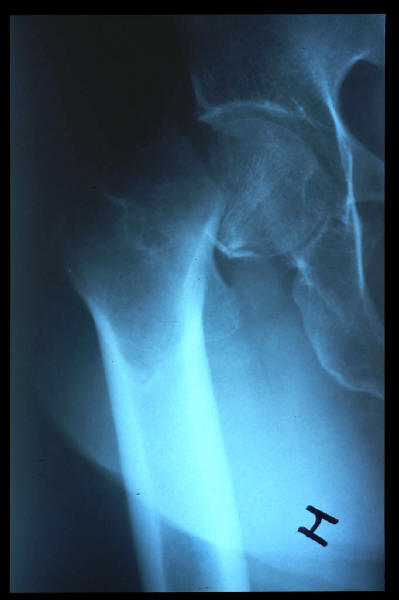

Fractura impactada de húmero .

Fractura de cuello de fémur.

Fractura de cuello de fémur